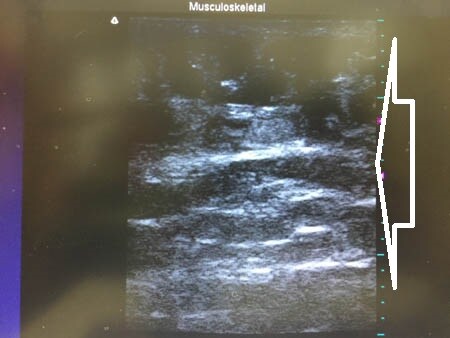

左腰。

↓ ↓ ↓